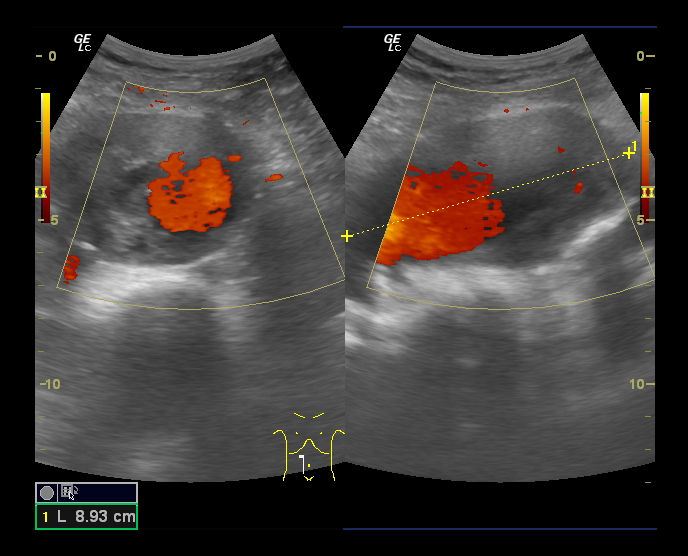

En Ecografía Clínica se aprecian, en la porción distal de la Aorta, imágenes sugestivas de aneurisma de Aorta abdominal con medidas aproximadas de 5.3 cm (anteroposterior) x 9 cm (longitudinal) con importante trombo intramural.

Diagnóstico diferencial: A la exploración física puede confundirse con otras masas abdominales como esplenomegalias o tumores. Con la eografía, la localización y captación doppler así como la pulsación característica hacen que resulte complicado confundir el diagnóstico.